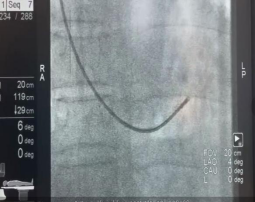

一院心内科李悦教授、梁兆光教授和谢荣盛副教授,心脏超声科、病理科和导管室等多学科专家会诊,决定为三位病人行右心漂浮导管及心内膜心肌活检术,为患者查明病因、精确诊疗。专家团队首先给予病人右心导管检查,测量上腔静脉压、右心房压、右心室压、肺动脉压、肺小动脉楔压及心输出量等参数。随后在X线结合超声引导下,利用心肌活检钳经颈静脉途径夹取心肌组织,进行病理检测、电镜观察及免疫组化诊断。